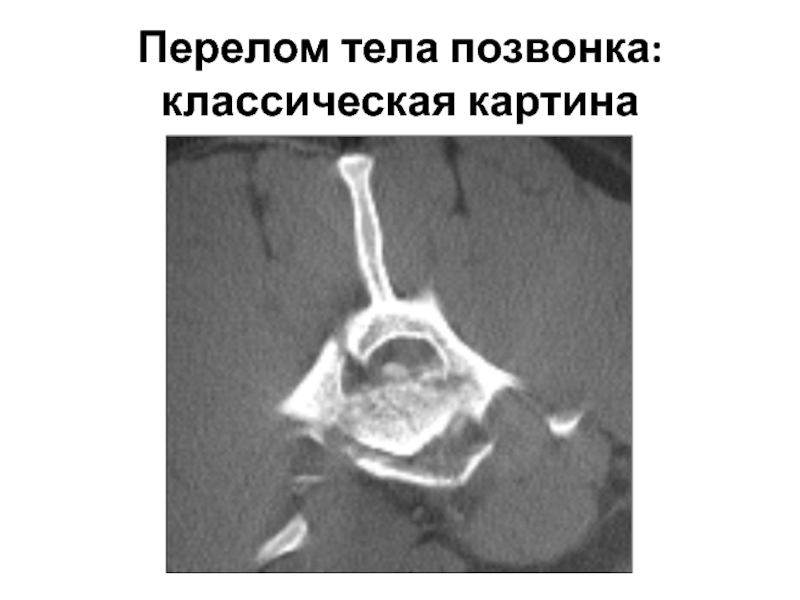

Компьютерная томография в неврологии презентация - 86 фото